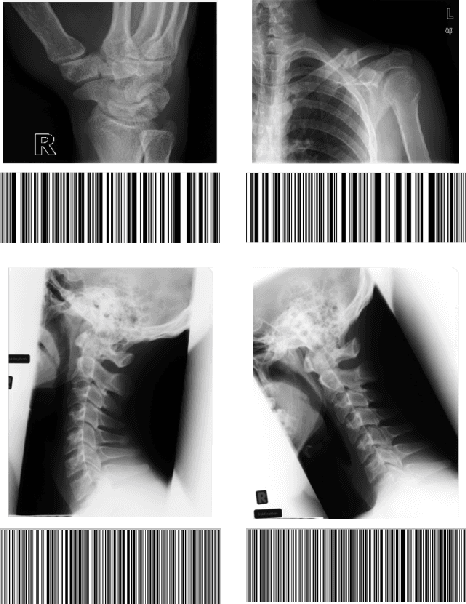

Abstract:In recent years, with the explosion of digital images on the Web, content-based retrieval has emerged as a significant research area. Shapes, textures, edges and segments may play a key role in describing the content of an image. Radon and Gabor transforms are both powerful techniques that have been widely studied to extract shape-texture-based information. The combined Radon-Gabor features may be more robust against scale/rotation variations, presence of noise, and illumination changes. The objective of this paper is to harness the potentials of both Gabor and Radon transforms in order to introduce expressive binary features, called barcodes, for image annotation/tagging tasks. We propose two different techniques: Gabor-of-Radon-Image Barcodes (GRIBCs), and Guided-Radon-of-Gabor Barcodes (GRGBCs). For validation, we employ the IRMA x-ray dataset with 193 classes, containing 12,677 training images and 1,733 test images. A total error score as low as 322 and 330 were achieved for GRGBCs and GRIBCs, respectively. This corresponds to $\approx 81\%$ retrieval accuracy for the first hit.

Abstract:In recent years, advances in medical imaging have led to the emergence of massive databases, containing images from a diverse range of modalities. This has significantly heightened the need for automated annotation of the images on one side, and fast and memory-efficient content-based image retrieval systems on the other side. Binary descriptors have recently gained more attention as a potential vehicle to achieve these goals. One of the recently introduced binary descriptors for tagging of medical images are Radon barcodes (RBCs) that are driven from Radon transform via local thresholding. Gabor transform is also a powerful transform to extract texture-based information. Gabor features have exhibited robustness against rotation, scale, and also photometric disturbances, such as illumination changes and image noise in many applications. This paper introduces Gabor Barcodes (GBCs), as a novel framework for the image annotation. To find the most discriminative GBC for a given query image, the effects of employing Gabor filters with different parameters, i.e., different sets of scales and orientations, are investigated, resulting in different barcode lengths and retrieval performances. The proposed method has been evaluated on the IRMA dataset with 193 classes comprising of 12,677 x-ray images for indexing, and 1,733 x-rays images for testing. A total error score as low as $351$ ($\approx 80\%$ accuracy for the first hit) was achieved.